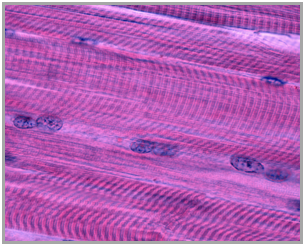

Muscle tissue is a specialized type of tissue in the body that plays a crucial role in movement by contracting and generating force. The primary function of muscle is to convert chemical energy, primarily stored in the form of adenosine triphosphate (ATP), into mechanical energy, which results in movement. Additionally, muscle activity generates heat, contributing to the maintenance of body temperature, a concept previously discussed in the context of homeostasis.